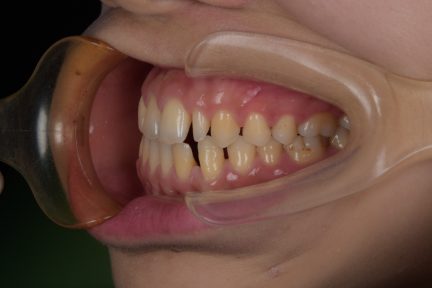

Classe I, morsure bord à bord, espacement, diastème

État initial

- Il s'agit d'un cas d'orthodontie combinée à une réparation esthétique.

- Il était nécessaire d'améliorer l'occlusion et la répartition de l'espace grâce à Invisalign et d'améliorer la forme et la beauté des dents du patient grâce à une restauration esthétique.

- Avant le traitement orthodontique, le patient a utilisé la conception esthétique DSD pour répartir l'espace, et l'espace dispersé en dehors de la zone esthétique a été ajusté par le mouvement proximal de la dent postérieure.